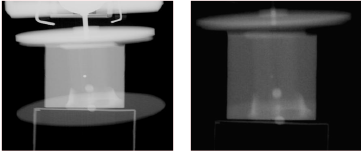

3.1 진단용 CT를 이용한 기준영상과 gating을 적용한 4차원 진단용 CT 영상의 분석

(a)

(b)

(c)

inner ball in the BB phantom (a) transverse plane image (b) sagittal plane image (c) coronal plane image

BB 팬텀이 움직이지 않고 정지된 상태에서 진단용 CT로 촬영된 영상이 기준 영상이다. 이 기준 영상에서 BB 팬텀의 ball의 size는 SI, AP, RL 방향 모두 2.4mm 로 나타났으며 이는 partial volume effect로 인하여 실제 크기인 2mm보다 조금 크게 보이는 것으로 판단된다. 호 흡을 완전히 내쉰 상태와 같은 위상인 완전호기 위상 4 차원 진단용 CT 영상에서 ball size는 SI 3.3mm, AP 3.3 영상의 왜곡도 분석 2.9mm, LR 2.7mm로 정지영상에서의 ball size와는 그 영상의 왜곡 정도를 비교하기 위하여, gating이 적용 차이가 1mm 이내로 나타났다. 된 3개의 이미지 시리즈와 gating이 적용되지 않은 기존 Gating을 적용한 4차원 진단용 CT 영상을 기준 영상 의 kV-CBCT 이미지 시리즈를 비교 분석하였다. 과 비교하였을 때 BB 팬텀의 중심 ball의 위치 오차는 BB 팬텀의 중심단면에서 팬텀의 가로방향과 세로방 0.7mm(SI방향), 0.3mm(AP방향), 0.1mm(RL방향)로 모 향의 중간비율을 구하였으며, 그 왜곡도는 기준영상에서 두 1mm 이내로 나타났다. 0%, 4차원 진단용 CT에서 4.7%, gating이 적용된 kV-CBCT 2.1%, gating이 적용된 MV-CBCT 2.21% 정 3.2 Gating을 적용하지 않은 kV-CBCT 영상 도로 양호한 수준을 보이고 있다. 그러나 기존의 방법인 의 분석 gating을 적용하지 않은 kV-CBCT에서는 400%로 나타 기존의 상품으로 사용되고 있는 kV-CBCT는 gating 났다[Table 1]. 을 적용하지 않고 있으며 기준 영상과 비교하였을 때 BB팬텀의 중심 ball의 위치 오차는 13.2mm(SI방향), 3.4 CBCT gating 정확도 분석 9.1mm(AP방향), 1.2mm(RL방향)로 큰 차이를 보였다 Gating이 적용된 각 CBCT 영상의 gating 정확도를 [Fig. 8]. 이는 gating을 적용하지 않은 상태에서 확인하기 위하여, 기준영상과 gating이 적용된 각 CBCT kV-CBCT 영상은 gating을 적용한 영상보다 영상의 왜 에 촬영 된 BB 팬텀 중심 ball의 위치를 pixel 단위로 그 곡이 매우 심하게 나타남을 의미한다. 이러한 상황은 임 중첩정도를 확인하였다. 기준 영상과의 일치도는 상 현장에서 부정확한 영상의 획득으로 치료부위의 부정 kV-CBCT 80.33%, MV-CBCT 79.6%로 매우 양호하게 확한 위치정보를 얻어 set-up의 오차가 발생하는 원인이 나타났다[Table 1, Fig. 9]. 된다.